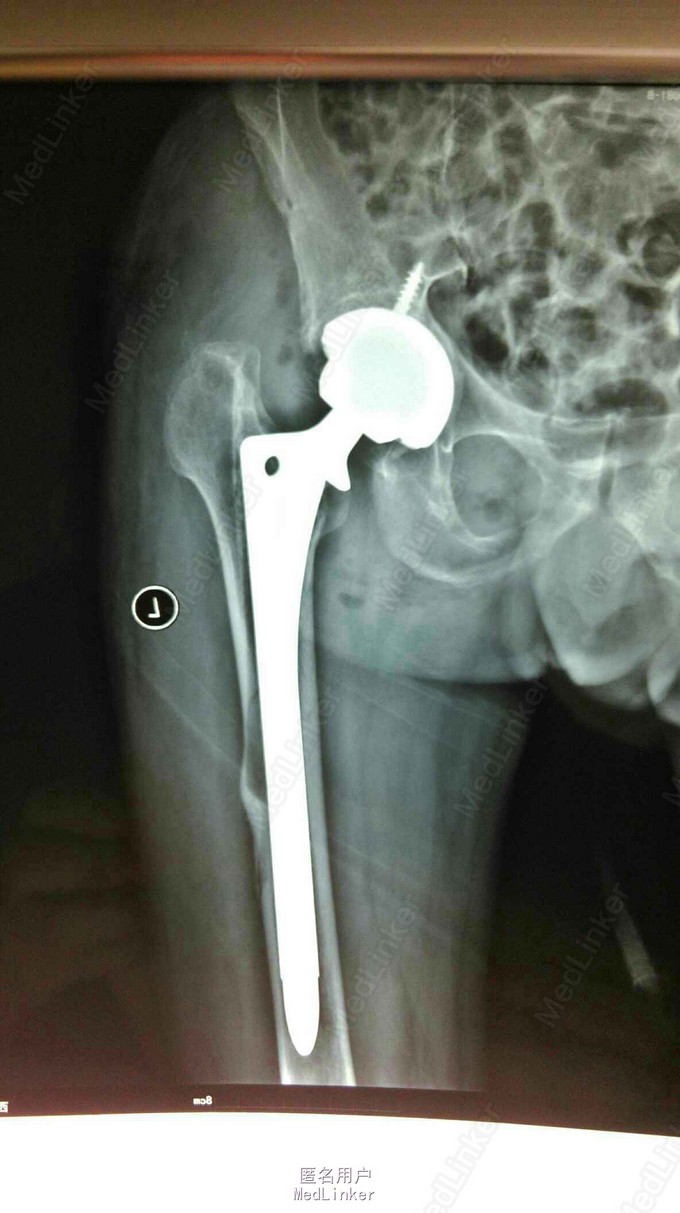

髋关节置换术后15年,疼痛2年。 15年前左股骨头坏死,在外院行股骨头置换术,2年前左下肢短缩,左髋关节疼痛,活动受限。

左下肢短缩4cm,左髋关节外展受限,叩痛阳性,左下肢血运,感觉正常。

左股骨头置换术后假体松动 完善术前检测后行髋关节翻修术,术中髋臼侧打压植骨,术后左下肢短缩1cm ,顺利出院。